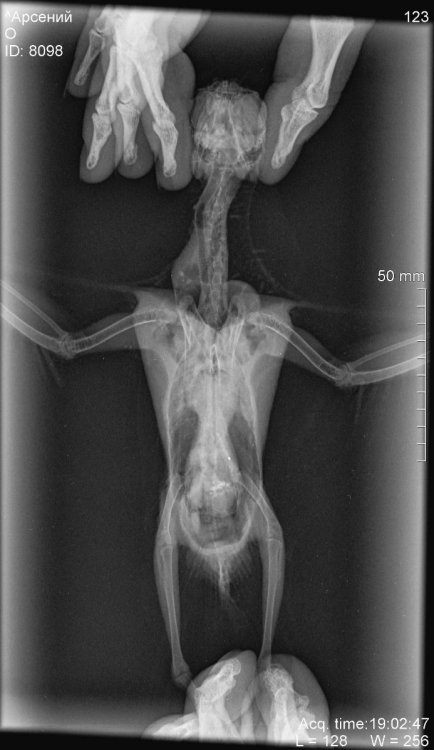

1.jpg

2.jpg

3.jpg

4.jpg

5.jpg

с этим и с рентгеном-это только к врачу Зосе